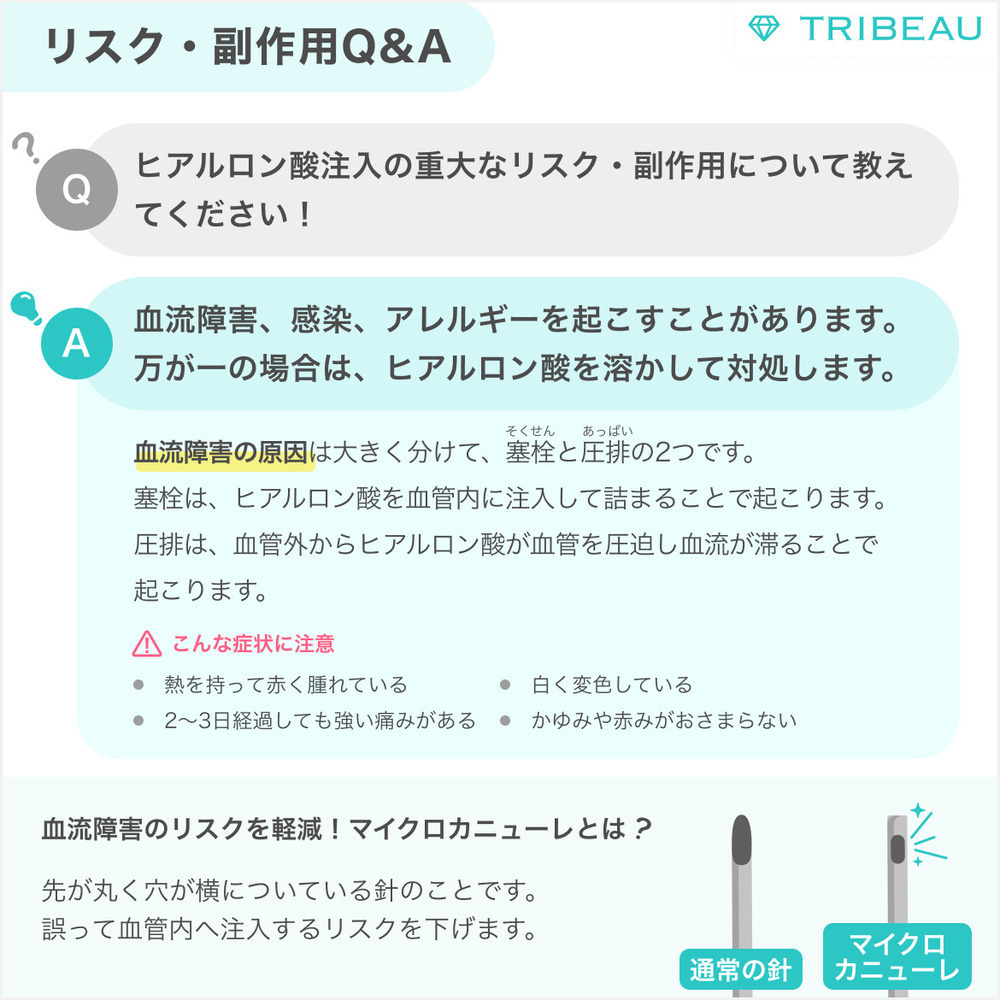

リスク・副作用

内出血腫れ赤みむくみ痛み感染塞栓

※この他にも予期しない症状が現れる可能性があるので、術後異常を感じた際には速やかにご相談ください。